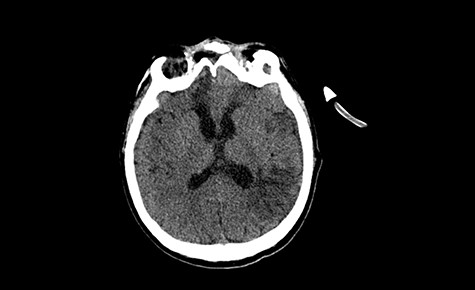

Head CT—state before VP shunt implantation. (Department of Neurosurgery own material).

A 49-year-old patient presented after surgical treatment of nasal polyps, with headache and consciousness disorders (behavioral changes, drowsiness and allophenic orientation disorders). Computed tomography (CT) scan showed (Fig. 1) a presence of blood in fluid spaces, widening of the ventricular system (without active hydrocephalus features) and presence of air in the frontal horns of the lateral ventricles and features of cerebral edema. Due to the subarachnoid hemorrhage, an angio-CT and CT scan was performed, showing no vascular malformation. The patient's condition deteriorated with a drop in Glasgow Coma Scale (GCS) to 9, strongly expressed meningeal syndrome and a fever of > 38°C. In the performed cerebrospinal fluid examination a typical picture for bacterial infection, cultures negative. Treatment was implemented in accordance with the neuro-infections algorithm. Clinical and laboratory features of neuroinfections have withdrawn. The neurological condition of the patient improved to GCS 11. Control head CT (Fig. 2) showed enlargement of the ventricular system with cerebrospinal fluid transudation.

After improvement of patient’s neurological status, a CT scan of the head revealed enlargement of the ventricular system with the features of cerebrospinal fluid transudation (Fig. 2), thus the patient has been qualified for a VP shunt implantation (Fig. 6).